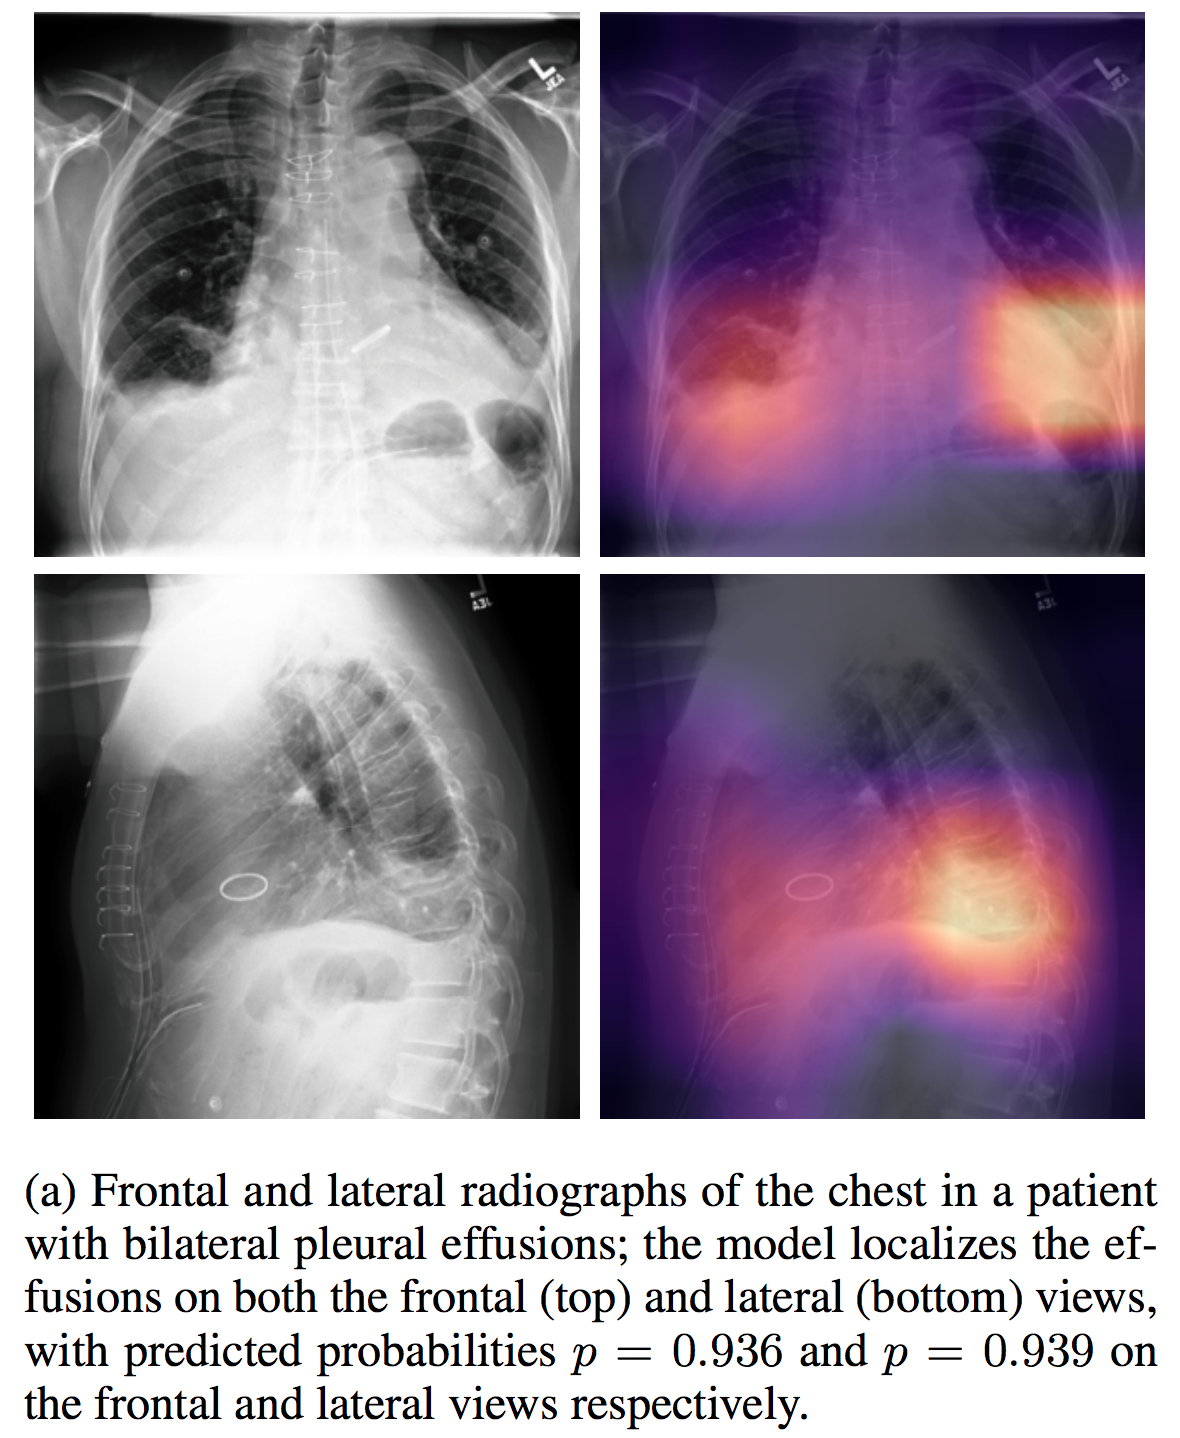

chest-x-pert.png